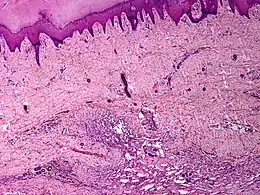

Description de cette image, également commentée ci-après

angiomatose cutanée